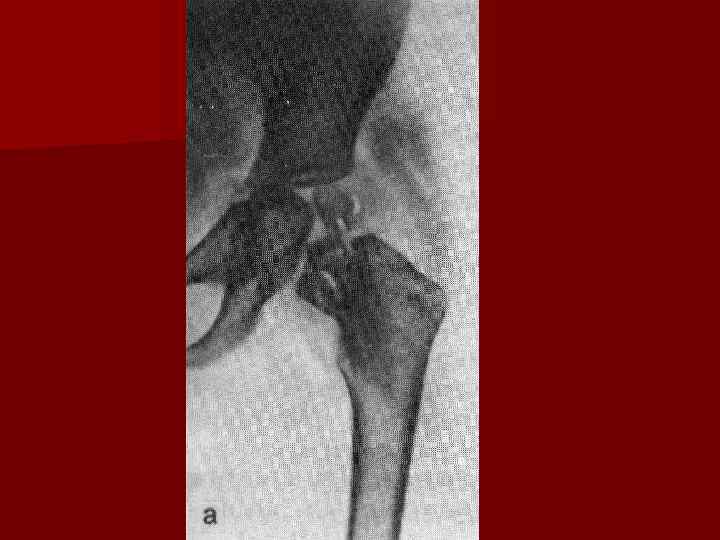

Рентгенограмма левого тазобедренного сустава (переднезадняя проекция) при туберкулезном коксите в постартритической фазе: головка бедренной кости полностью разрушена, шейка бедренной кости истончена и склерозирована, вертлужная впадина расширена за счет деструкции ее свода, видны секвестры (1), в наружных отделах мягких тканей бедра — натечный абсцесс (2).